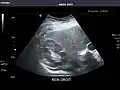

Abdominal Ultrasound (Full Exam)

STRUCTURED REPORT

(Technique: Transabdominal ultrasonography; Device: Toshiba Aplio XG)

Liver: Diffusely homogeneous and normal in echogenicity. No focal mass or contour nodularity. No intrahepatic biliary ductal dilatation.

Portal Vein: Patent main portal vein.

Gallbladder: No stones, wall thickening, or pericholecystic fluid.

Common Bile Duct: Nondilated measuring 1.3 mm at the level of the porta hepatis.

Pancreas: Visualized portions unremarkable.

Spleen: Normal in size.

Kidneys: Right and left kidneys measure 11.5 cm and 12 cm in length respectively. No hydronephrosis. Small left lower pole kidney cyst.

Ascites: None.

Aorta: Visualized portions normal in caliber, 16 x 15 mm.

IVC: Normal.

IMPRESSION:

Normal abdominal ultrasound.

Left kidney -